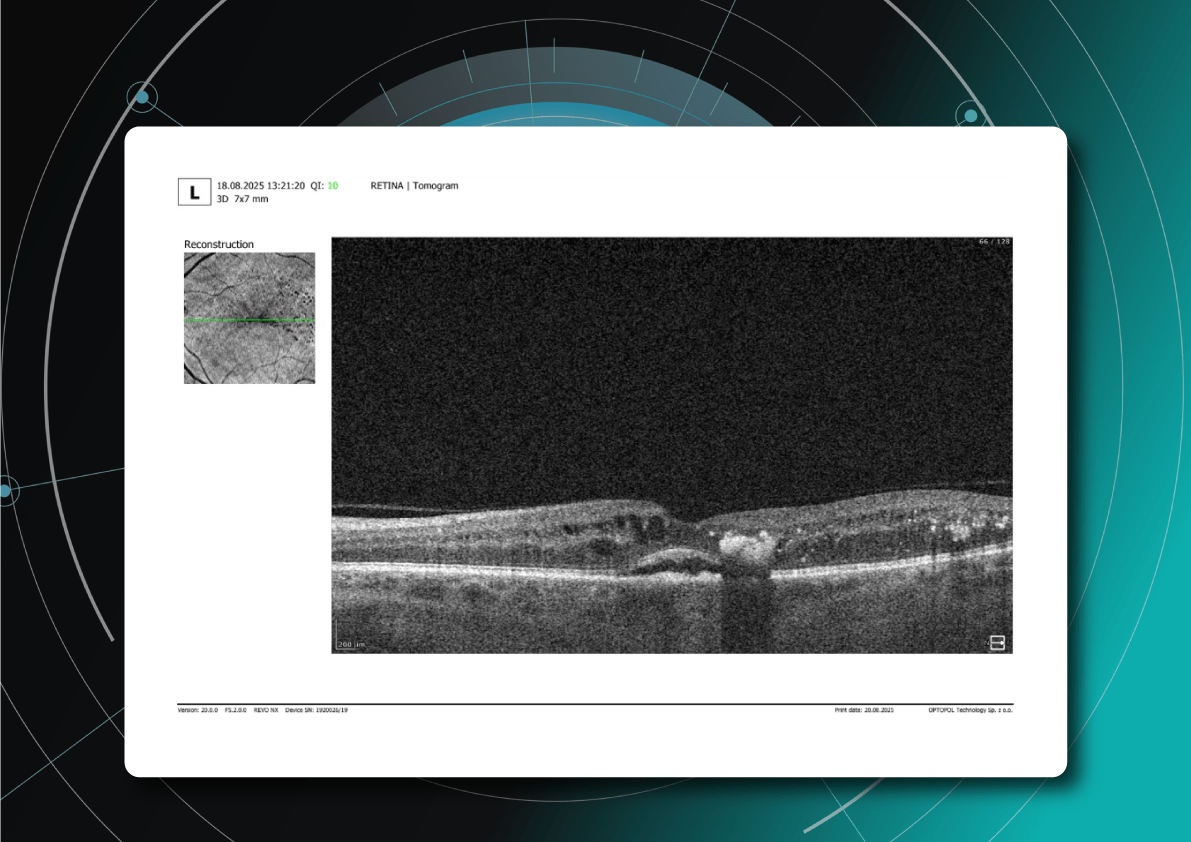

Dr. Maria Sampalis, OD, the owner of Sampalis Eye Care, Rhode Island, utilizes two such programs in her practice. To support her specialization in dry eye management, she employs CSI Dry Eye. Additionally, she uses Altris AI, an AI-powered platform for OCT scan analysis, to provide a second opinion and enhance diagnostic accuracy.

Dr. Sampalis finds that the Dry Eye software allows her and her staff to analyze symptoms and images comprehensively, improving patient care, time savings, and increasing diagnostic precision. See how OCT AI works here.

Her patients also appreciate Altris AI, which analyzes OCT scans for over 70 pathologies and biomarkers while also calculating the risk of developing glaucoma.

Working with specialized software solutions improves diagnostic accuracy and aids in patient education. Visual representations of their conditions, facilitated by these technologies, empower patients with a clearer understanding, leading to increased treatment compliance.

Eye Place, an optometry center in Columbia, also leverages Altris AI, among other cutting-edge technologies. They capture images using the Topcon Maestro2 OCT and use Image Net6 software to export DICOM files to the Altris AI platform.

Beyond AI-powered OCT analysis, Eye Place utilizes state-of-the-art diagnostic tools, such as 3D OCT equipment, to screen for serious conditions, including glaucoma, diabetes, and macular degeneration. Furthermore, they work with AdaptDX Pro, a technology capable of detecting macular degeneration earlier than traditional methods.

AI-assisted readings of OCT scans are already helping not only with pathology detection but also with the analysis of its progression or response to treatment. This represents a new approach to monitoring, where practitioners no longer need to sift through various patient notes but can directly compare reports from previous examinations and observe how, for instance, shadowing has changed in micrometers.

Measuring treatment progress: biomarkers tracking, pathology progression

Imaging biomarkers are a particularly attractive option for clinical practice due to their non-invasive and real-time nature. Quantitative measurements of retinal thickness, fluid volume, and other biomarkers relevant to diseases like diabetic retinopathy and age-related macular degeneration aid in treatment monitoring.

OCT reports with customized measurements and selected biomarkers, retinal layers, or segments allow for precise focus on treatment monitoring and patient response to therapy. This personalized approach enhances clinical decision-making by highlighting each case’s most relevant information.

Subsequent follow-up visits will then display the most relevant picture, highlighting the most pertinent biomarkers for tracking a particular pathology (wet AMD in our example) and comparing their volume, progression, or regression through visits.

Another helpful option is retinal layer segmentation, which focuses solely on the retinal layers of interest for the specific case.

This level of customization empowers clinicians with a comprehensive yet targeted view of the patient’s condition. It saves time from manually detecting anomalies on scans and facilitates informed decision-making and personalized treatment plans.